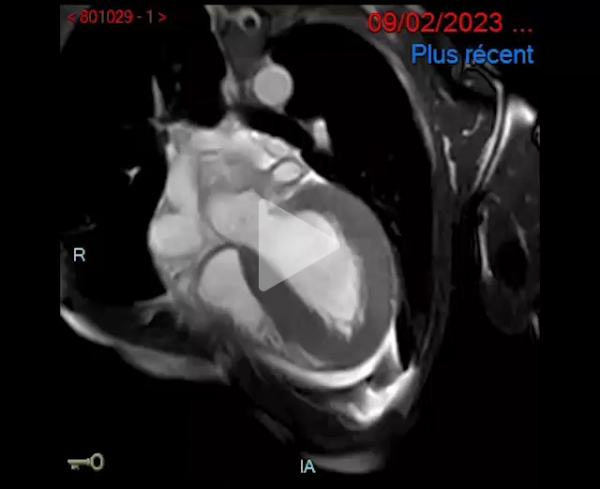

IRM cardiaque en février 2023 :

- Cardiomyopathie hypertrophique évoluée

- Dysfonction biventriculaire sévère, FEVG 19%, FEVD 22%

- VG dilaté

- IRM en faveur d'une pathologie de surcharge : pas d'argument pour un Fabry en IRM

- Faisceau d'arguments plutôt évocateur d'une amylose cardiaque

Vidéo 1